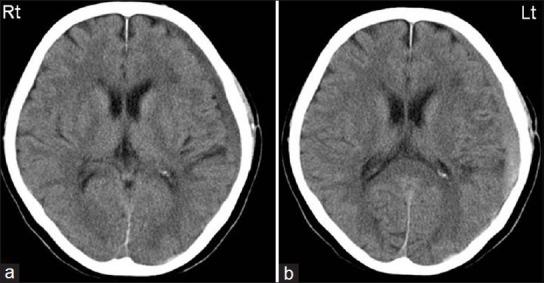

EMBOLIZATION WAS PERFORMED IN THE THREE PATIENTS WHO HAD REFRACTORY CSDH WITH REPEATED RECURRENCE: The procedure was performed after burr hole irrigation of the hematoma in two patients and before the irrigation in one patient. In the two CSDH patients at risk of recurrence, embolization was performed when signs of recurrence appeared. The timing of embolization differed for each patient. However, in all the patients, the hematoma tended to decrease in size, and no recurrence was observed.

对3例难治性CSDH反复复发患者进行了栓塞术:2例患者在血肿钻孔冲洗后进行该操作,1例患者在冲洗前进行。对于2例有复发风险的CSDH患者,在出现复发迹象时进行栓塞。每位患者的栓塞时机不同。然而,所有患者的血肿均有缩小趋势,且未观察到复发。